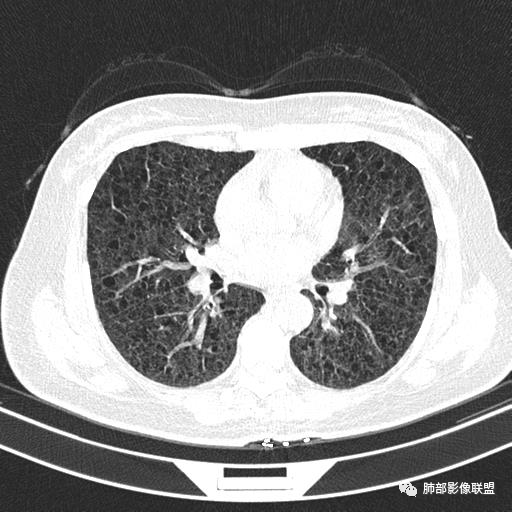

中年女性,不吸烟

双肺弥漫囊腔,累及肋膈角,囊腔形态相对规则单一。

CT平扫示双肺弥漫分布大小不等囊状薄壁透光区,无内、中、外带分布差异,间质稍示增厚。拟LAM

中年女性育龄期妇女,咳嗽气喘,无吸烟史,有苯吸入史。影像:双肺弥漫均匀小囊腔,无明显分布优势,囊腔形态欠规则,壁薄,部分囊腔边缘血管征,伴双肺弥漫磨玻璃影,无结节,考虑lam,鉴别苯中毒肺损伤,囊腔多有分布优势,小叶中心分布为主,形态规整等

女,46,活动性气喘1年。苯吸入史半年。胸部CT:两肺弥漫囊腔,上至肺尖,下至肋膈角,形态类似小囊腔。考虑:LAM,鉴别LIP,BHD,PLCH等。

CT表现:双肺弥漫大小不等的薄壁囊腔,囊壁<2mm,外形规则,血管影多位于囊腔周围,囊腔之间肺组织正常,随着疾病进展到晚期,囊腔变大、增多,不可胜数,囊腔可融合成较大的囊,与肺气肿相似,形成间质性肺纤维化。部分病例可出现结节影。